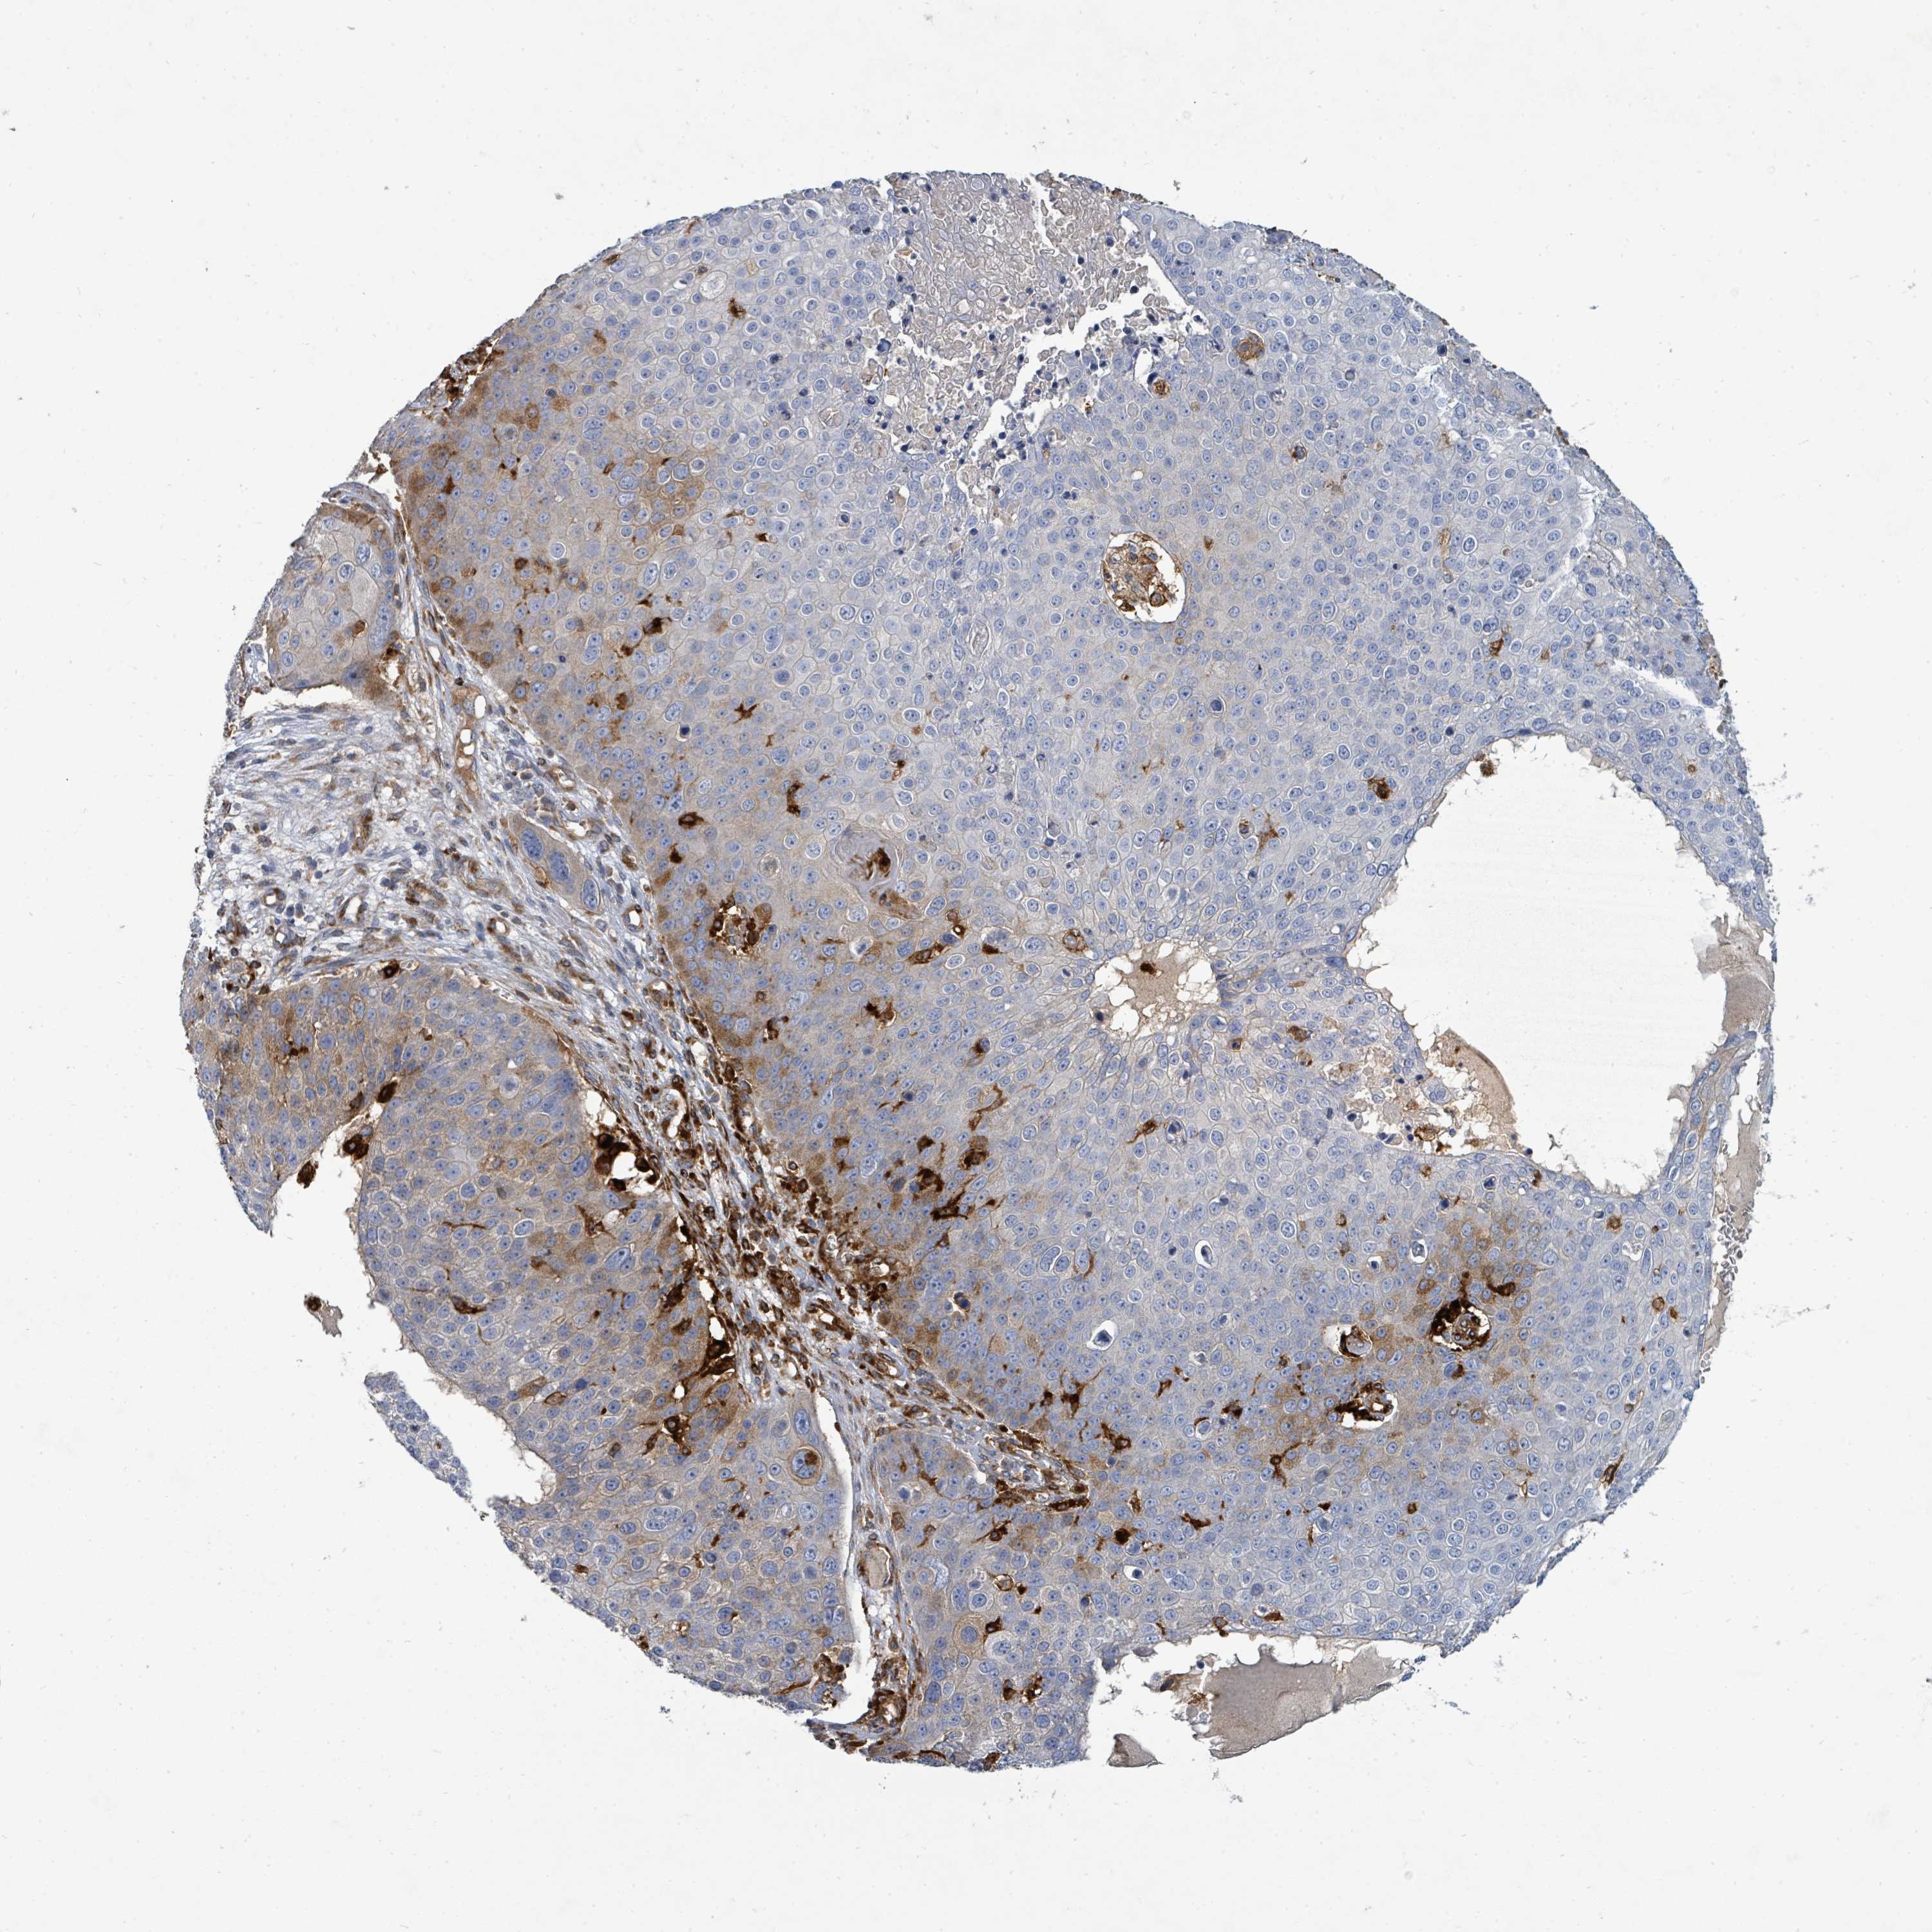

SKIN CANCER - Protein expressioni

A mouse-over function shows sample information and annotation data. Click on an image to view it in a full screen mode. Samples can be filtered based on level of antibody staining by selecting one or several of the following categories: high, medium, low and not detected. The assay and annotation is described here.

Each image is clickable and will lead to virtual microscopy that enables deeper exploration of all samples and also displays staining intensity scores, fraction scores and subcellular localization as well as patient and tissue information for each sample.

Antibody CAB080338

Squamous cell carcinoma, NOS